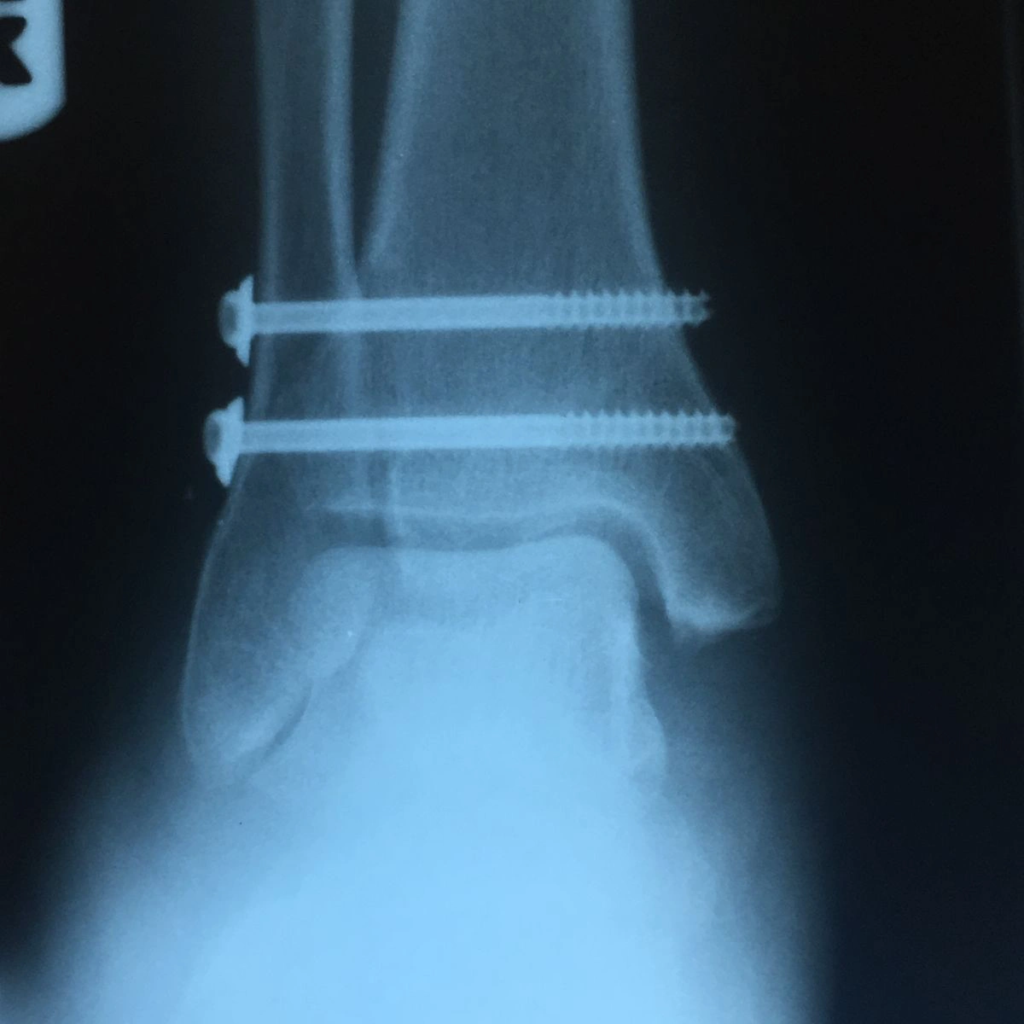

Most high ankle sprains don’t require surgery; however, in severe cases, if a ligament has been completely torn, the standard surgical procedure is to insert a screw between the tibia and fibula to hold the two bones together.

This relieves pressure on the ligaments and allows them to scar in place and heal.